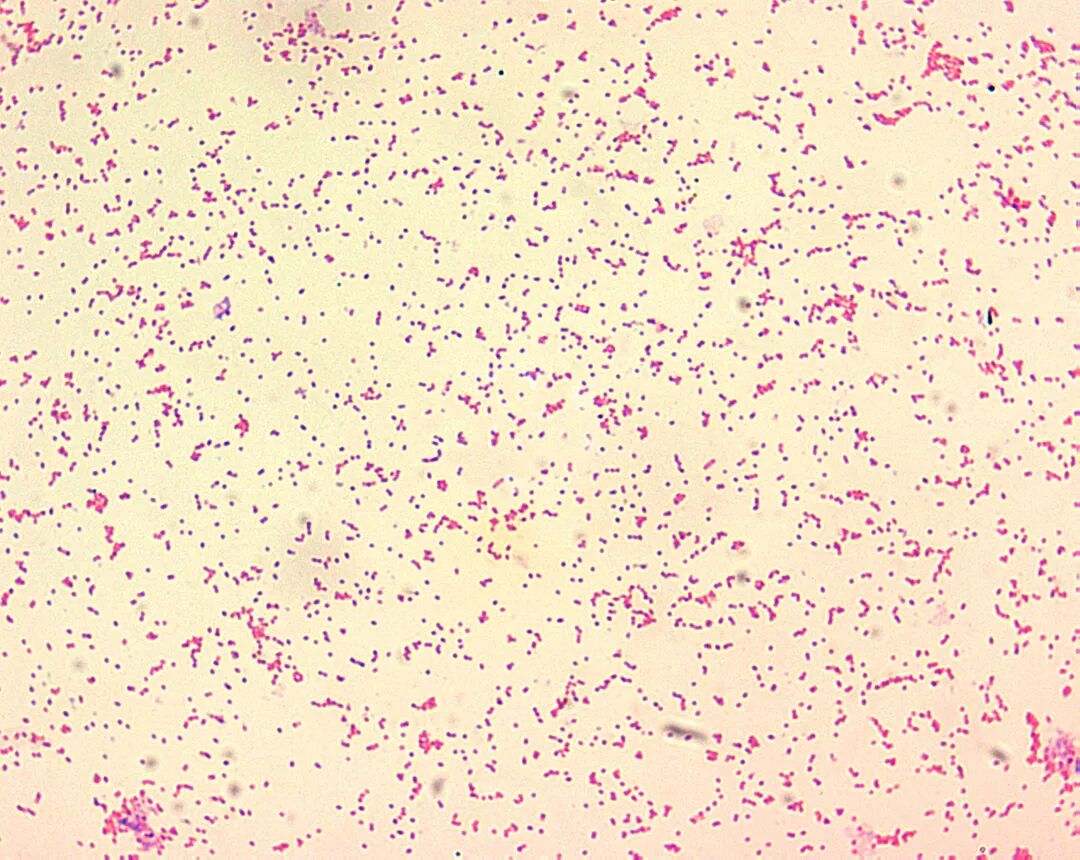

短小的阴性杆菌

布鲁菌是不能运动的需氧短小杆菌,兼性细胞内寄生,其直径和长度分别为0.5-0.7μm和0.6-1.5μm。革兰染色表现为单个的短小革兰阴性球杆菌。除了导致兔热病的土拉弗朗西斯菌之外,布鲁菌可能是临床实验室中可见的最小革兰阴性微生物。布鲁菌无荚膜、芽孢和鞭毛。

在革兰染色上,它们显示为革兰阴性球杆菌的致密团块,并且非常难以鉴定。